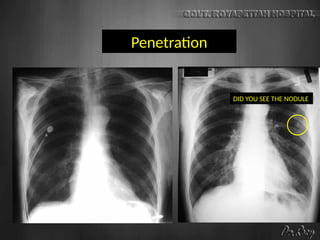

Penetration

DID YOU SEE THE NODULE